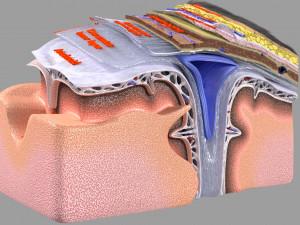

Brain with meninges scalp detailed labelled 3D 3D मॉडल

A blend model of brain along with its covering layers (meninges), skull bone and scalp labelled in detail and anatomically precise. The parts depicted are white, gray, pia, arachnoid, dura, bone, skin, fat, aponeurosis, periosteum, falx cerebri and more.

The material is high resolution image textures and normal maps based on non overlapping UVs. The texture and normal maps are packed with the blend file itself.